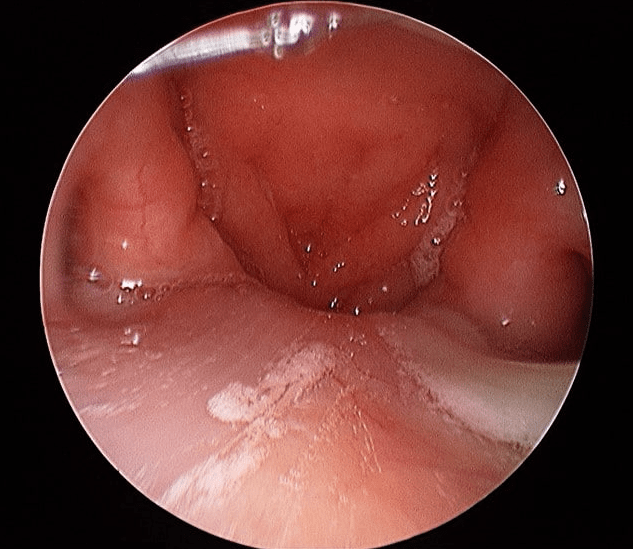

How an ENT Specialist Evaluates Globus

Assessment includes:

- Detailed history

- Mouth & neck exam

- Flexible nasoendoscopy

- Thyroid assessment

- Imaging if needed

This ensures serious conditions are excluded.

Globus sensation is often benign but never ignored. Direct throat visualisation is essential to exclude cancer and structural disease. Accurate diagnosis prevents unnecessary medication and anxiety.